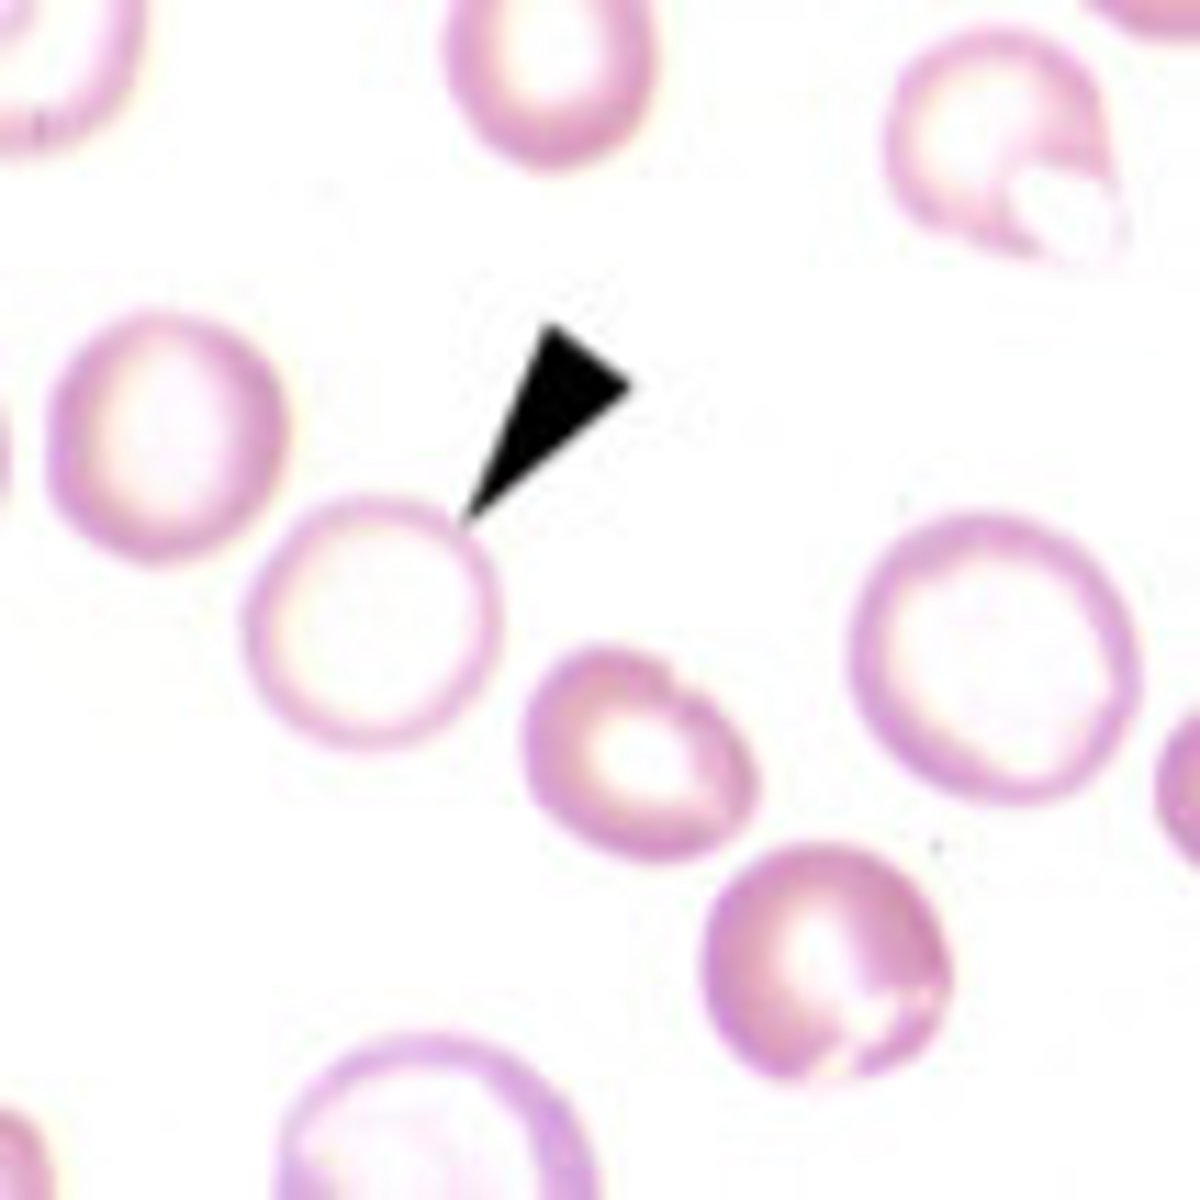

hypochromasia

increased level of central pallor

-decrease hemoglobin concentration

torocytes

AKA punched out cells

- "donut" hole presentation

--artifact